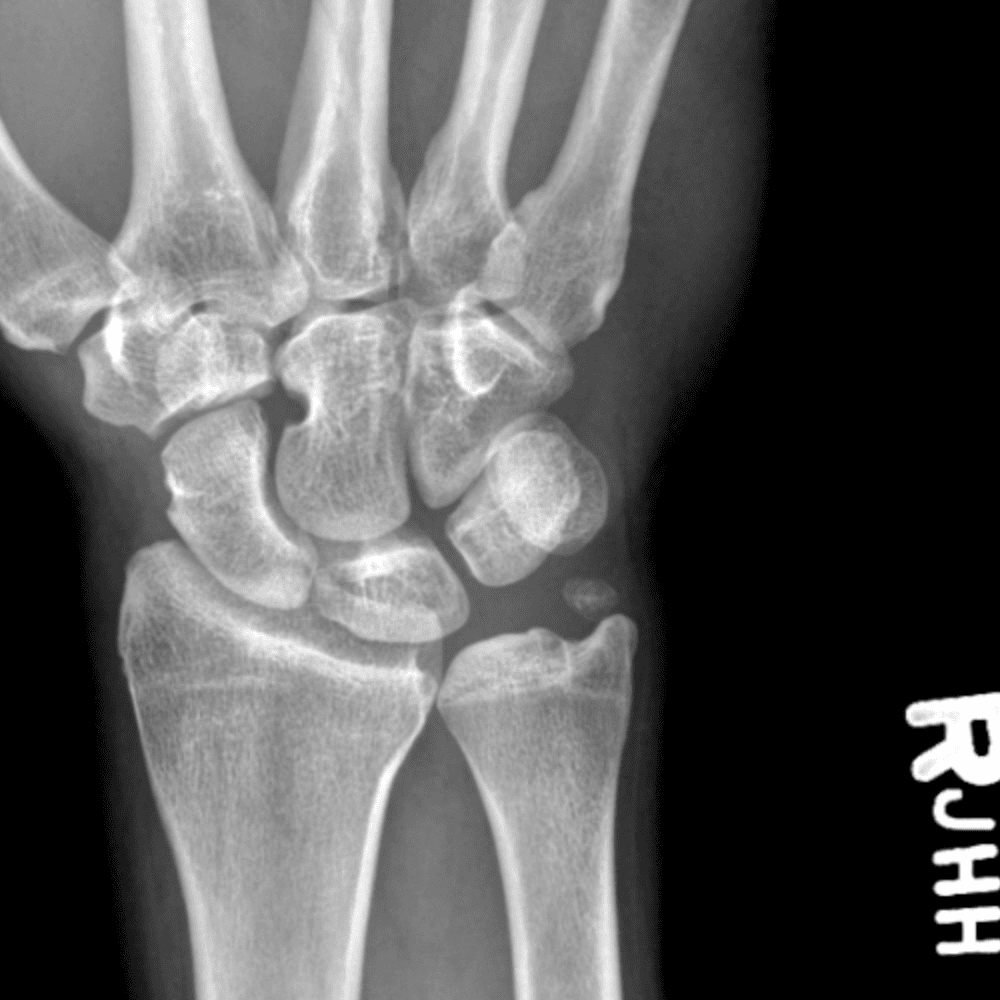

Simuliert den Dienst durch subtile oder schwierige Fälle und einige Normalbefunde.

30 Fälle